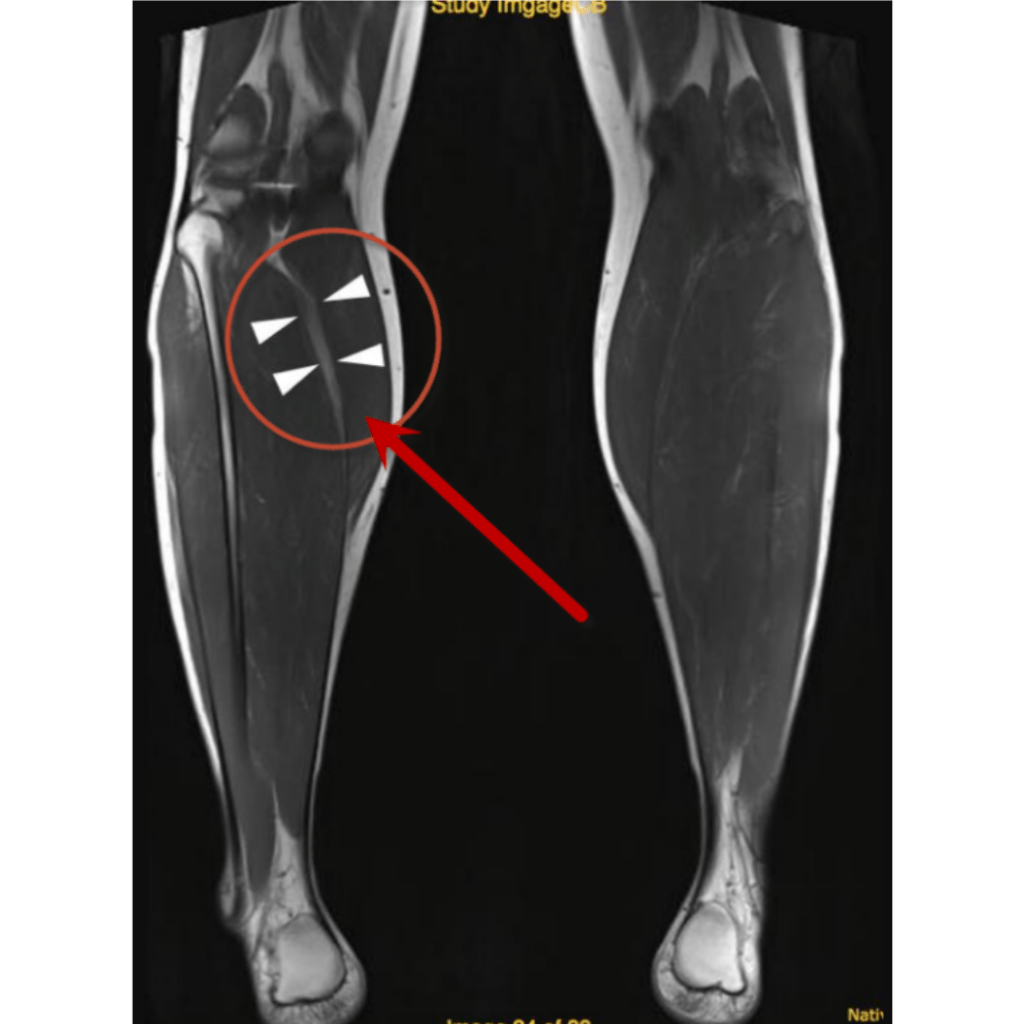

El diagnóstico de esta afectación dependerá mucho de su localización, en caso de sospecha de compromiso en un músculo superficial se puede hacer uso de ecografía (ultrasonido), en tejidos más profundos es más eficiente una resonancia magnética.

Resonancia magnética

Ruptura parcial Grado II